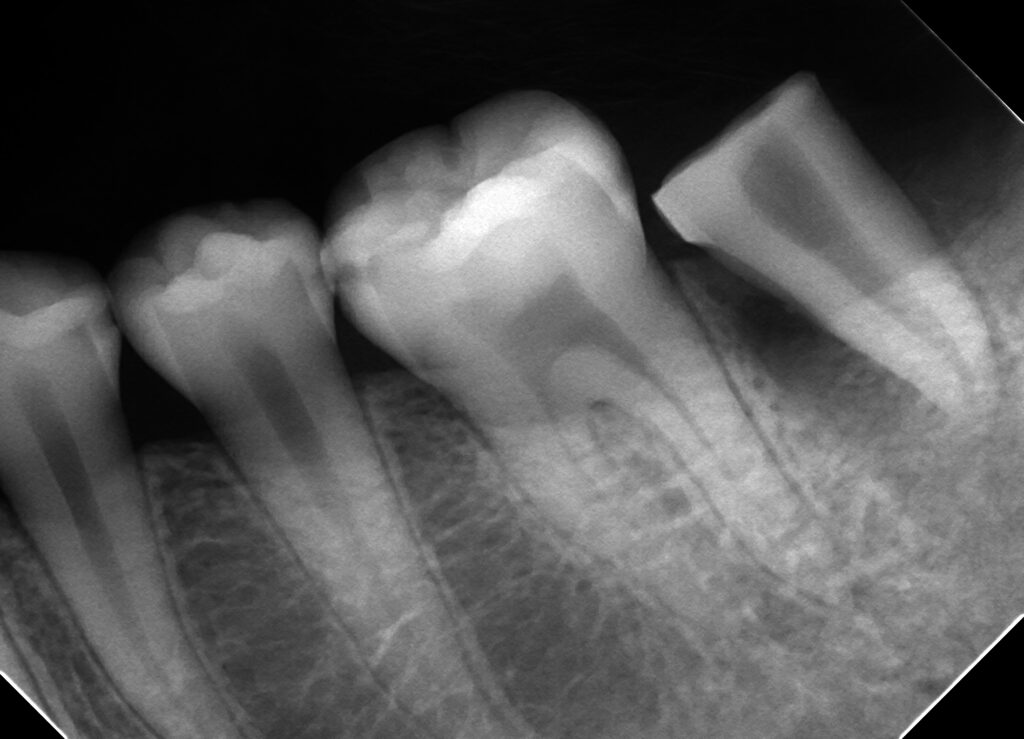

移植直後の拡大した写真です